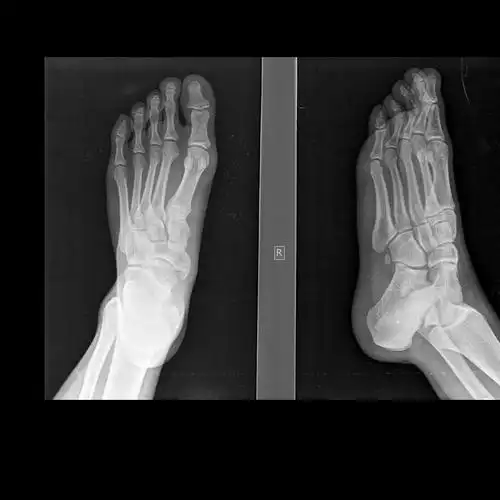

请教各位10765右足正斜位片

学习《x线读片指南》骨,关节系统——足